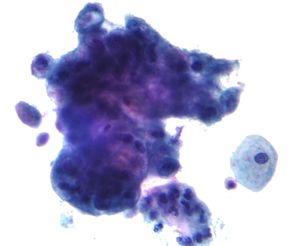

자궁경부암은 라틴 아메리카, 사하라 이남 아프리카, 아시아 일부 지역 여성에게 가장 흔한 암 3위 안에 든다. 자궁경부 세포 검사는 자궁경부의 비정상적인 병변을 감지하여 여성이 암으로 발전하기 전에 치료를 받도록 하는 것을 목표로 한다. 양질의 선별 검사와 후속 치료가 자궁경부암 발병률을 최대 80%까지 줄이는 것으로 나타났기 때문에, 대부분의 선진국에서는 현재 성적으로 활동적인 여성에게 3~5년마다 파파니콜로 검사를 받도록 권장한다.[63] 핀란드와 아이슬란드는 일상적인 모니터링을 통해 효과적인 조직 프로그램을 개발했으며, 미국이나 캐나다와 같은 비조직적이고 기회적인 프로그램보다 적은 자원을 사용하면서 자궁경부암 사망률을 크게 줄이는 데 성공했다.[63]

칠레, 콜롬비아, 코스타리카, 쿠바와 같은 라틴 아메리카의 개발도상국에서는 1970년대부터 공공 및 민간 조직 프로그램 모두 여성에게 일상적인 세포 검사를 제공해 왔다. 그러나 이러한 노력은 이 국가에서 자궁경부암 발병률이나 사망률의 상당한 변화를 가져오지 못했다. 이는 아마도 낮은 품질과 비효율적인 검사 때문일 것이다. 그러나 1960년대부터 조기 선별 검사를 제공해 온 푸에르토리코는 1950년과 1990년 사이에 자궁경부암 발병률이 거의 50% 감소했고 사망률이 거의 4배 감소했다. 브라질, 페루, 인도, 그리고 조직적인 선별 검사 프로그램이 없는 사하라 이남 아프리카의 여러 고위험 국가들은 자궁경부암 발병률이 높다.[63]